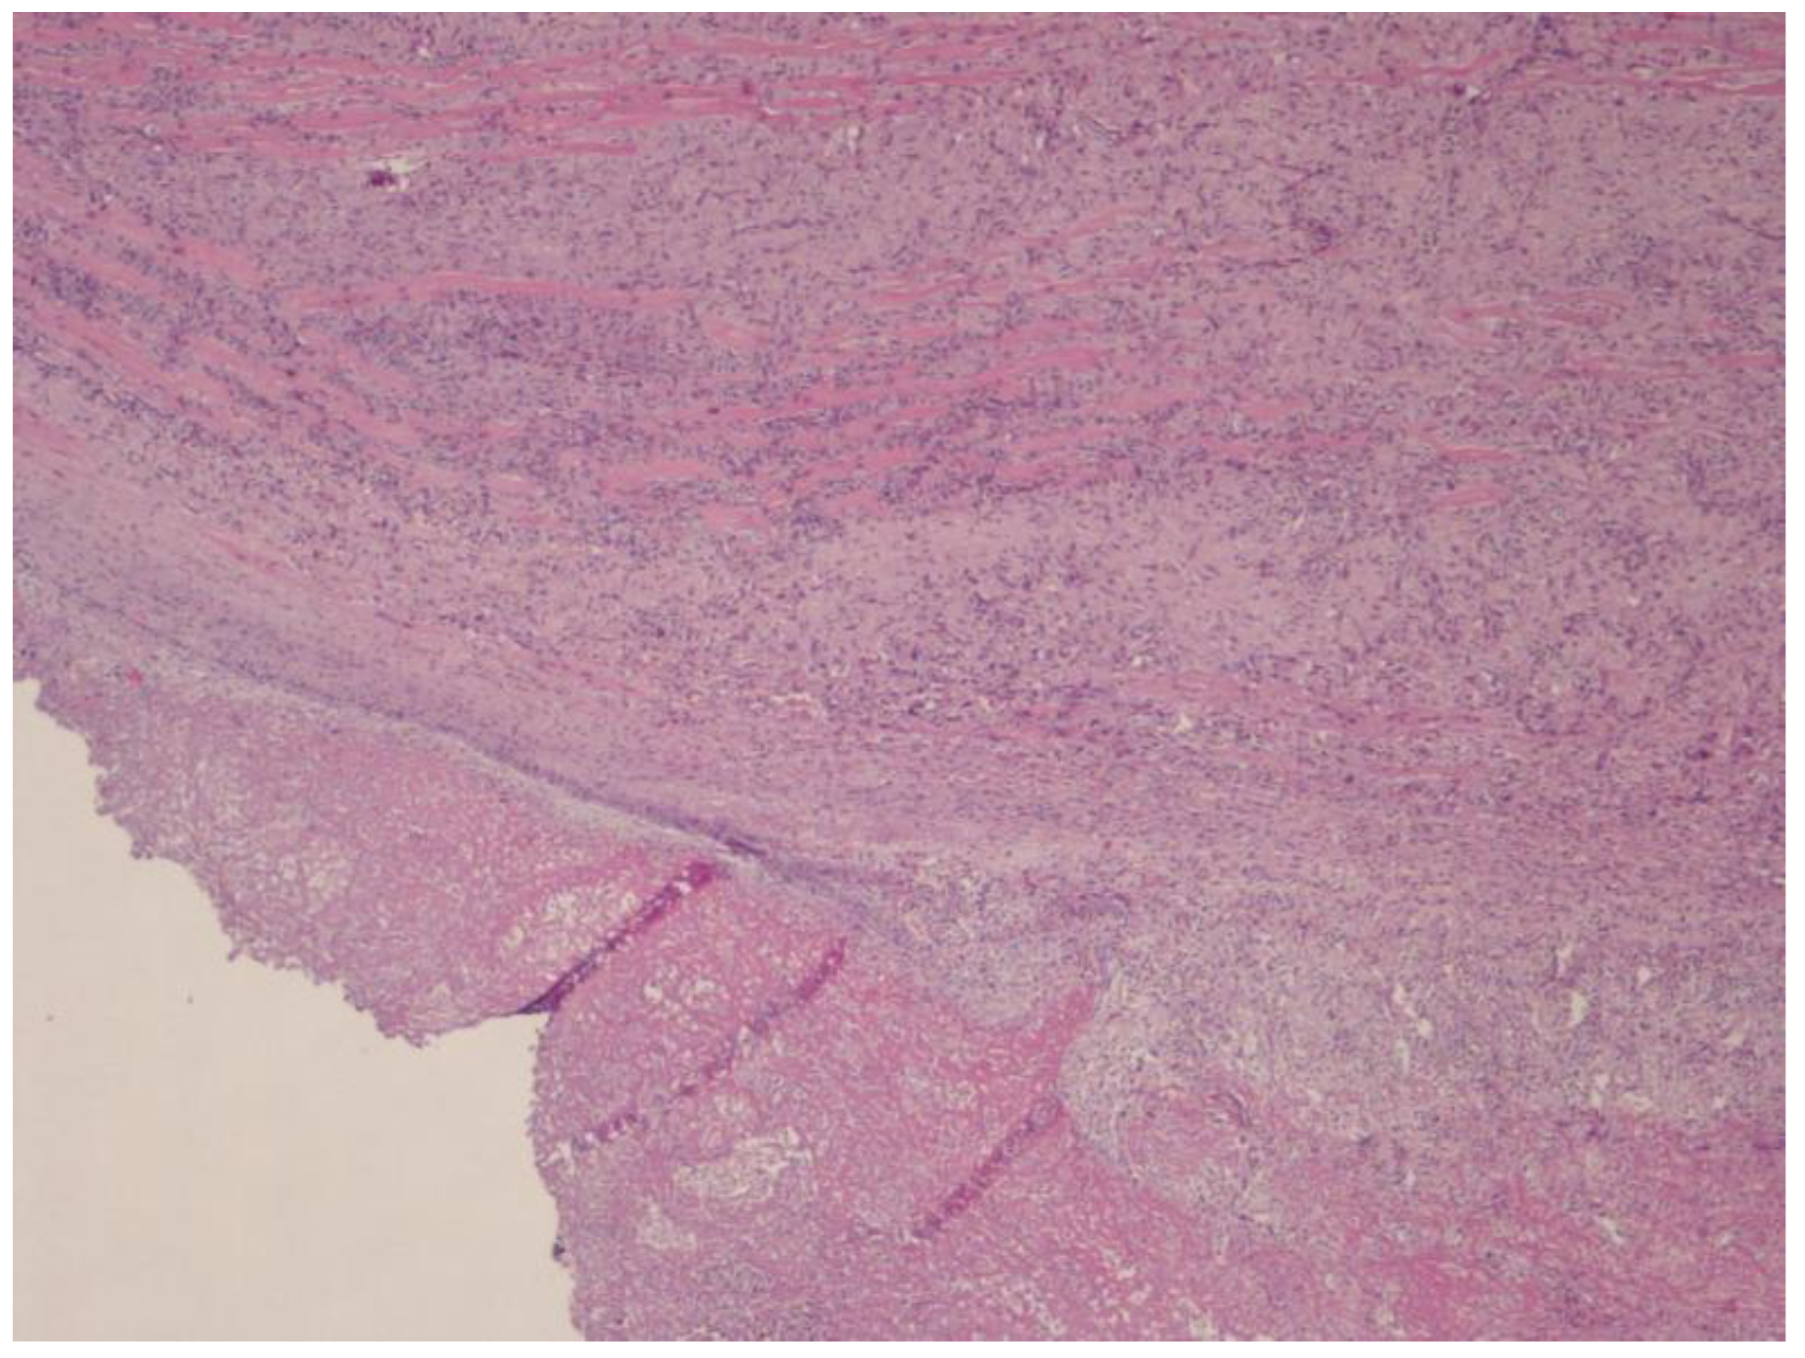

2.4. Histological Finding